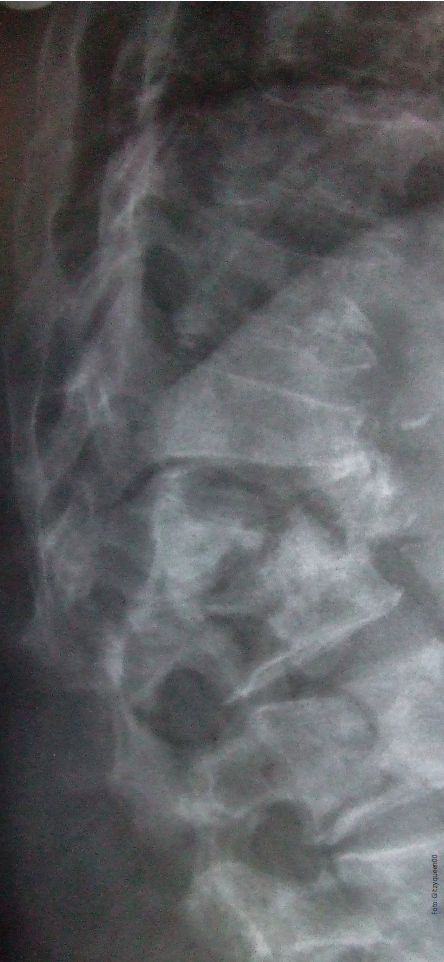

Figura 1 Hueso-tejido adiposo

Los osteoblastos y los adipocitos derivan de una línea celular mesenquimatosa común, (figura 1) y agentes que inhiben la adipogénesis estimulan la diferenciación de osteoblastos (producción de hueso) y viceversa.